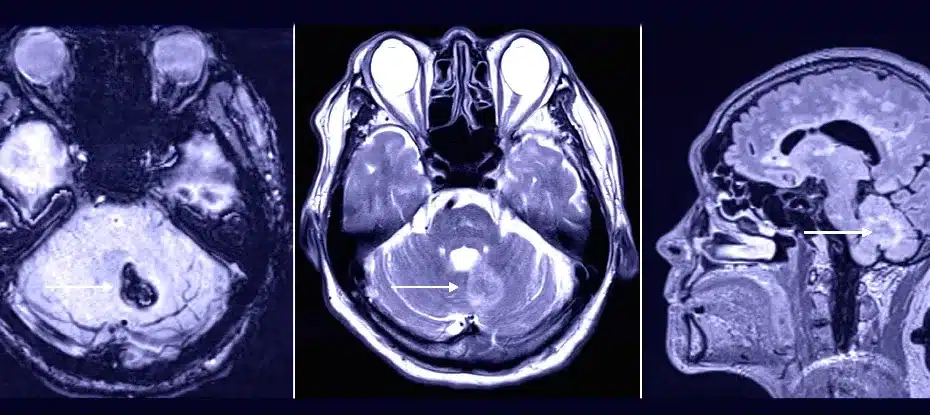

Visita ao dentista pode ter desencadeado sangramento cerebral raro em pacientedez 24, 2023Ciência, Notícias